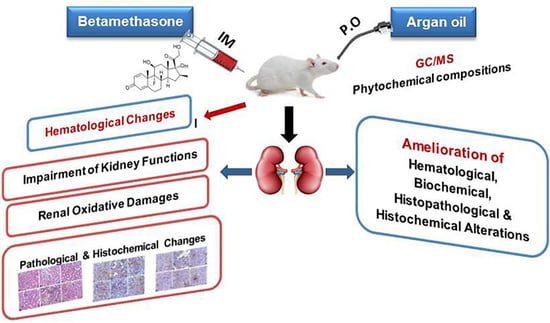

The Antioxidant, Anti-Apoptotic, and Proliferative Potency of Argan Oil against Betamethasone-Induced Oxidative Renal Damage in Rats

:Simple Summary

Abstract

1. Introduction

5. Conclusions